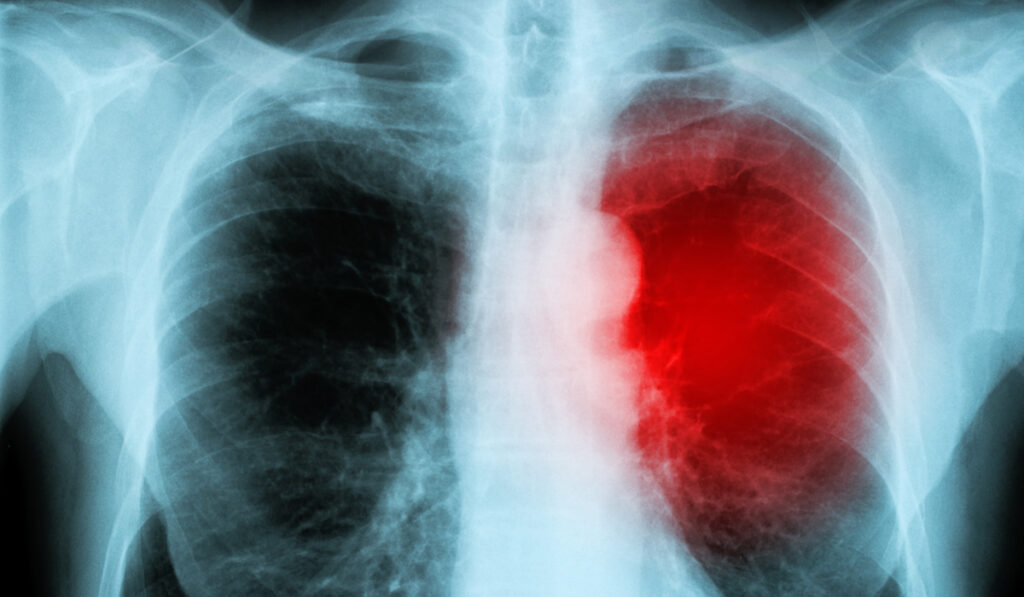

Myocarditis is an inflammation of the heart muscle, or myocardium, that weakens the heart, making it more difficult to pump blood effectively. While myocarditis can result from viral infections or various inflammatory conditions, it is most commonly a side effect of the COVID-19 mRNA vaccines.

According to the Cleveland Clinic, approximately half of people who suffer myocarditis will be dead within 5 years, while approximately 20% will be dead inside one year.